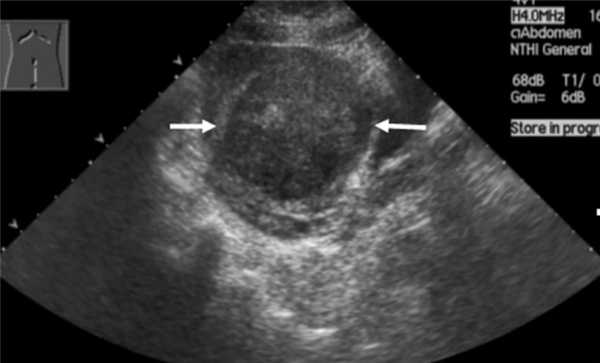

Номальная матка

Рис. 1. Нормальная матка.

Вторая фаза цикла. Миометрий однородный.

Толщина М-ЭХО соответствует дню цикла.

При оценке состояния матки при УЗИ можно определить:

- Положение матки.

В норме матка бывает либо отклонена в сторону мочевого пузыря, то есть кпереди (это положение матки называется anteflexio), либо отклонена в сторону прямой кишки, то есть кзади, - (retroflexio). - Размеры матки (продольный, передне-задний и поперечный). Средние значения размеров нормальной матки в длину от 4,0 до 6,0 см, переднее-заднего от 2,7 до 4,9 мм.Размеры тела матки варьируют в зависимости от возраста женщины, конституции и акушерско-гинекологического анамнеза.

- Состояние эндометрия (его толщина изменяется в зависимости от дня менструального цикла).

Сразу после окончания менструации эндометрий визуализируется в виде полоски толщиной 1-2 мм. Во второй фазе цикла толщина эндометрия (М-ЭХО) может составлять от 10 до 14 мм в среднем. - Состояние миометрия.

В норме миометрий должен быть однородным и не иметь в своей структуре патологических образований (миомы, аденомиоз и т.д.)